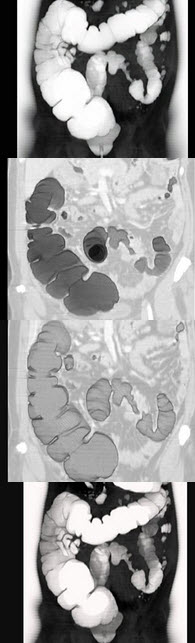

女,56岁,腹胀、腹痛、左下腹包块3月余,无肛门排气,影像检查如图,最可能的诊断是()

A .乙状结肠Crohn病

B .乙状结肠结核

C .乙状结肠腺癌

D .乙状结肠淋巴瘤

E .乙状结肠息肉

女,56岁,腹胀、腹痛、左下腹包块三月余,无肛门排气,影像检查如图,最可能的诊断

[单选题]女,56岁,腹胀、腹痛、左下腹包块三月余,无肛门排气,影像检查如图,最可能的诊断是()A .乙状结肠Crohn病B .乙状结肠结核C .乙状结肠腺癌D .乙状结肠淋巴瘤E .乙状结肠息肉